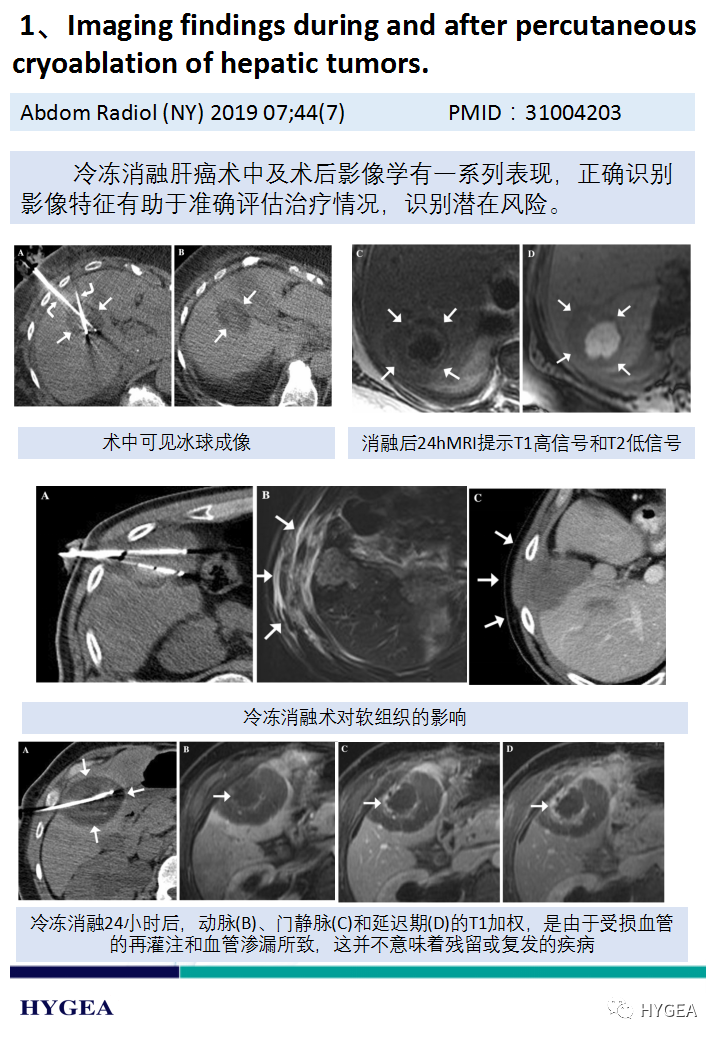

上一页:【海杰亚科研资讯】第188期——冷冻消融肝癌专题